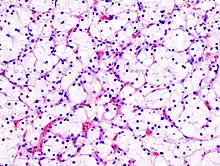

| Micrograph of the most common type of renal cell carcinoma (clear cell)—on right of the image; non-tumour kidney is on the left of the image. Nephrectomy specimen. H&E stain | |